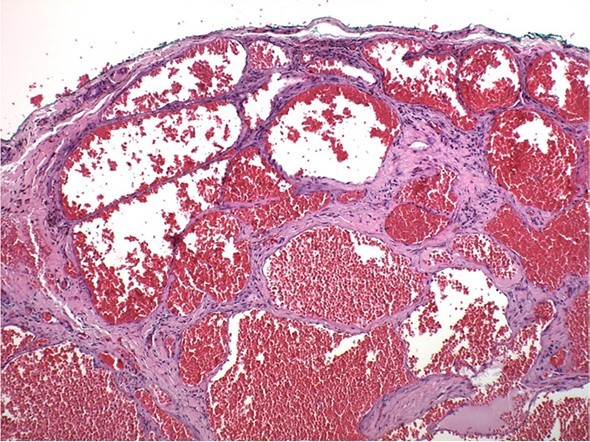

A 73-year old Asian female presented to the office for evaluation of a mass on the left cheek (Figure 1). Medical history reported by the patient included hypertension and osteoporosis. Medications included Losartan 50mg daily and Alendronate 70mg once per week. The patient stated that the mass appeared to be enlarging in size and was noticeable to her family. She denied pain or tenderness in the area of the cheek mass. Oral examination revealed a firm compressible submucosal mass in the left buccal vestibule of the mandible that did not blanche on digital pressure. The mass was negative for any bruit or vascular thrill. The surface mucosa overlying the mass was the same color as the buccal mucosa of the cheek (Figure 2). No imaging studies were indicated, as the mass was localized to the soft tissues of the cheek. The differential diagnosis included dermoid cyst, epidermoid cyst, and mucous retention cyst. The patient was informed of the clinical findings and the plan to remove the lesion as an in-office procedure. Under local anesthesia, using a #15 scalpel a mucosal incision was made and it was immediately observed that the dark purple mass was a suspected hemangioma (Figure 3). With careful blunt dissection, the purple-colored mass was completely excised and sent for histologic analysis (Figure 4). Histopathologic examination revealed a proliferation of irregular dilated capillary sinuses lined by flat endothelial cells. The sinusoidal spaces contained erythrocytes (Figure 5). The diagnosis was consistent with a cavernous hemangioma.

Figure 5.Histopathology of cavernous hemangioma. Note irregular sinusoids lined by endothelium containing erythrocytes. Hematoxylin and eosin, 400x.

In the oral cavity, cavernous hemangiomas are rare painless dark purple-blue colored soft tissue masses that will blanch with digital pressure. Hemangiomas can occur on the gingiva, soft and hard palate of the maxilla, lips, buccal mucosa, salivary glands, and jaw bones.4, 5They can appear as a smooth single or multiple lobulated compressible mass of variable size.1, 6, 7However, hemangiomas can mimic other tumor or cystic lesions as in this case report. In our patient, the surface mucosa was of normal color without the dark purple-blue color that is characteristic of hemangiomas. Histopathology reveals well developed capillary sinuses lined by endothelial cells separated by a connective tissue stroma. The dilated sinuses are often filled with erythrocytes.4, 8